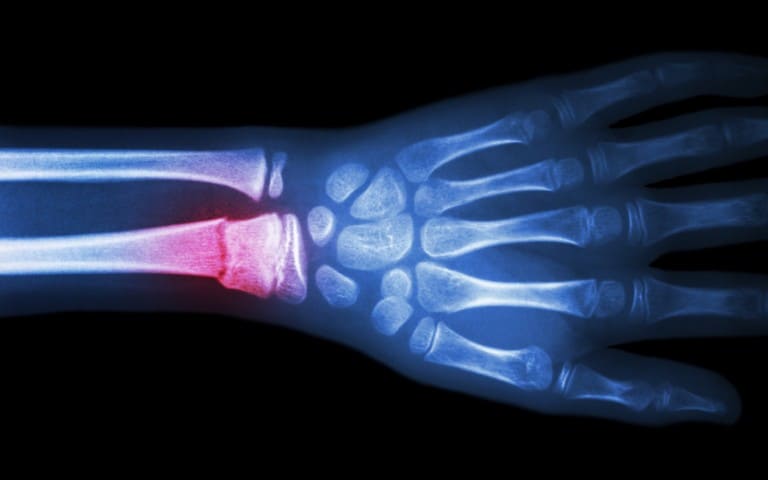

Wrist Fractures

Wrist Scaphoid Fractures

Carpal Injuries

Wrist Scaphoid Nonunion